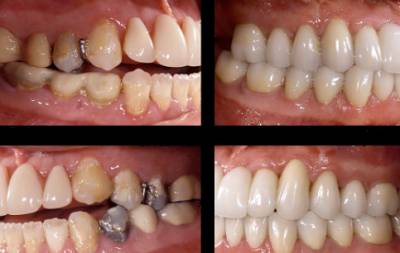

Фото до и после

Фото 2. Слева – фото до процедуры по удалению зуба, справа видны последствия – изменение прикуса.